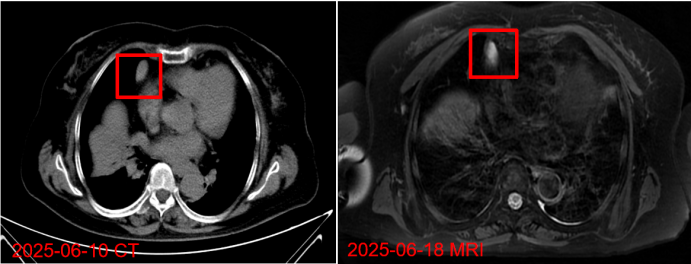

6月18日行MRI胸部增强扫描:前纵隔类圆形异常信号影,T2WI压脂序列呈高信号。考虑炎性包裹性积液,建议随访除外肿瘤性病变(图6)

图片

6  患者MRI与既往CT相比